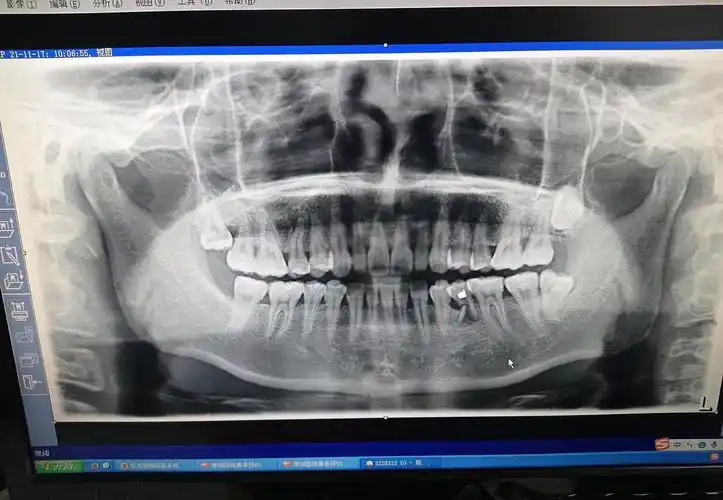

可见牙槽窝远中折断的牙根

看看我拍的片牙根断了